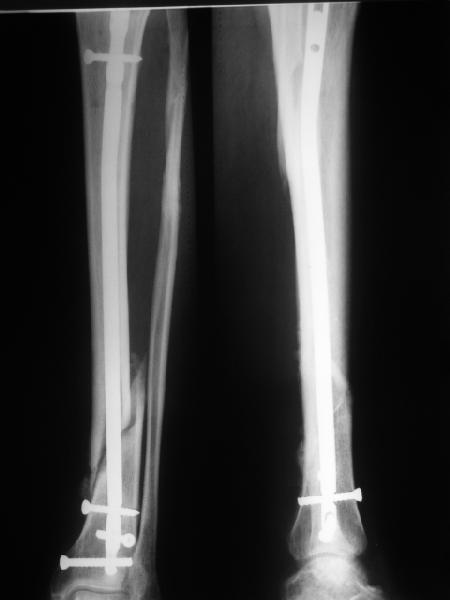

Re: неправильно фиксированный перелом

В приложении картинка пациента со сломанным внизу гвоздем. Начал лечение в другом учреждении. Еще и адвокат к тому же.

Динамизировали через 8 недель, а оно поползло больше, чем хотелось бы.